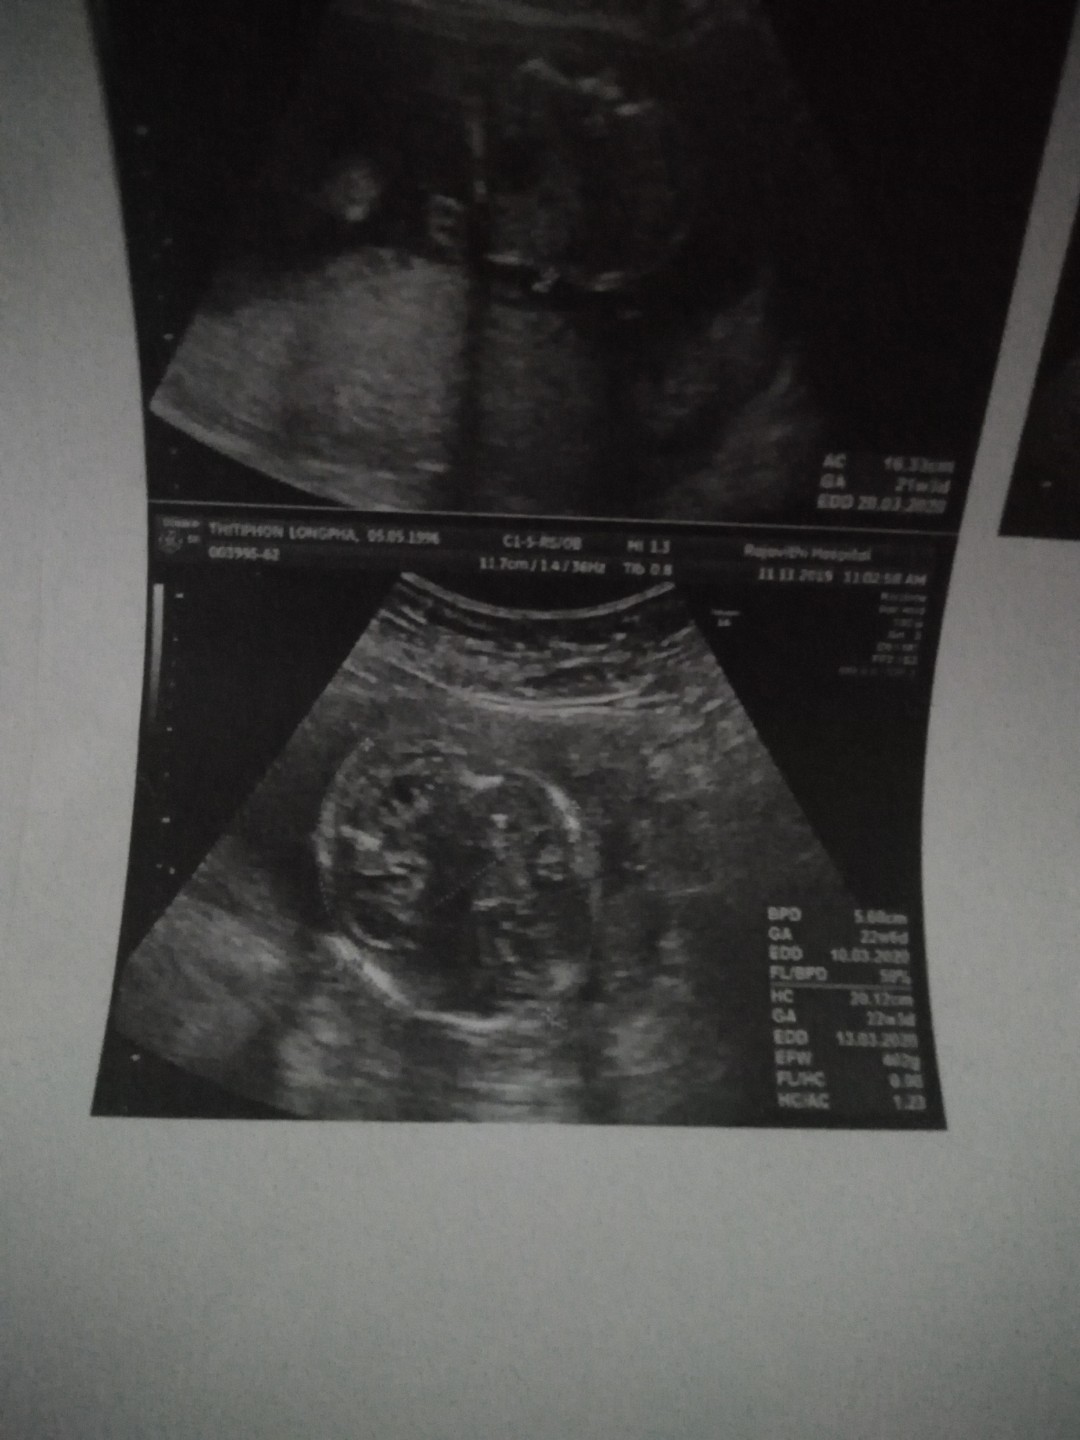

28 มีนา ต้นเดือนคุณหมอบอกผู้ชาย รอคอนเฟิร์มอีกทีต้นเดือนหน้าค่ะ